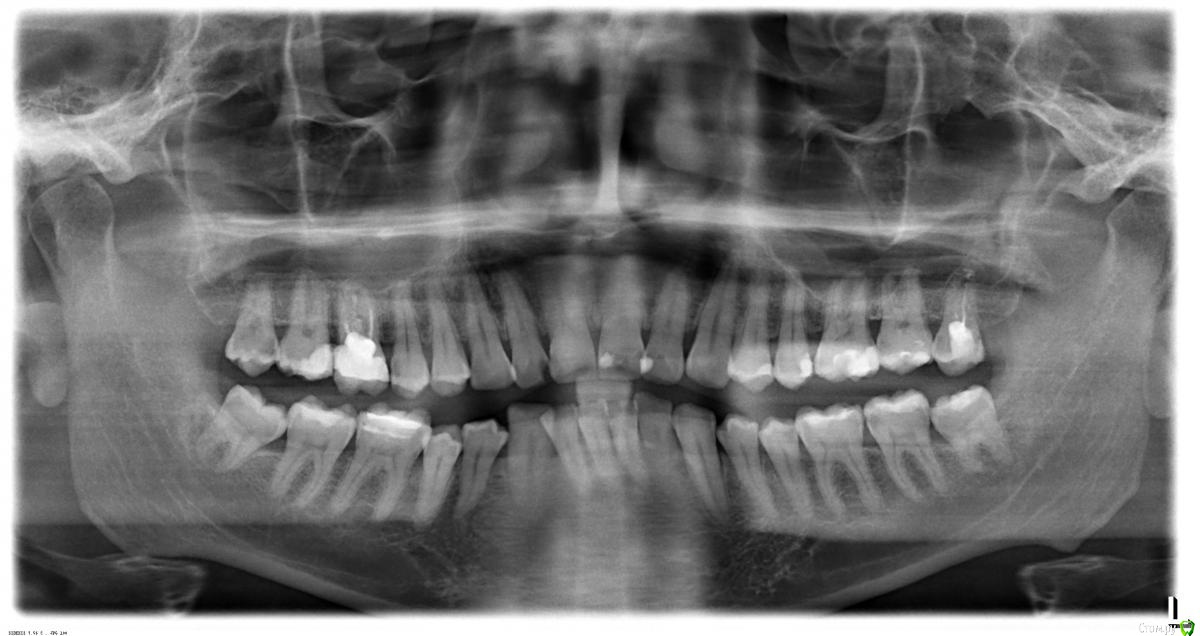

cxpoh Опубликовано 19 января, 2015 Поделиться Опубликовано 19 января, 2015 Здравствуйте. Щас лечу 17-й зуб. после удаления 18-го зуба, на 17-ом обнаружили дырочку кариеса. После визиографии 17-го зуба нашли кариес под пломбой. Сказали, сохранить можно, но зуб будет разрушаться, посоветовали протезирование металокерамической короной. Согласился на коронку. Произвели депульпацию зуба. При вскрытии пломбы завоняло тухлятиной. Залили Каласептом или Метапексом. Вопрос в том, сохранить зуб с штифтами и пломбами c наращиванием возможно? Ссылка на комментарий

red_butler Опубликовано 19 января, 2015 Поделиться Опубликовано 19 января, 2015 разделом ошиблисьпокажите снимок после лечения зуба 1 Ссылка на комментарий